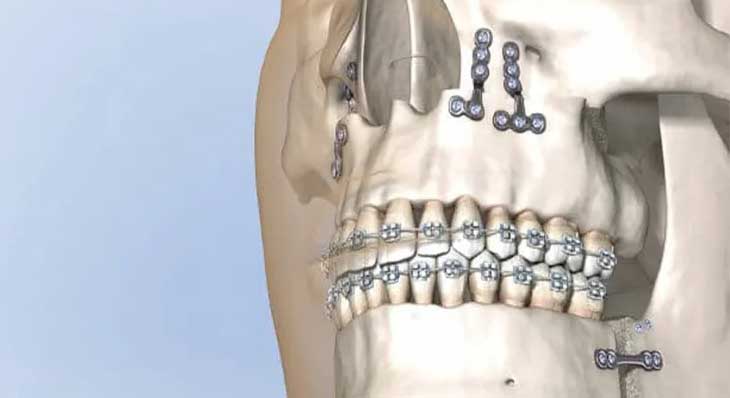

این مهم ترین مرحله است. متخصص ارتودنسی با استفاده از ارتودنسی ثابت، دندان ها را در هر فک به صورت مستقل صاف و مرتب می کند تا برای یک رابطه فکی جدید آماده شوند. - مرحله دوم: جراحی فک

پس از آماده شدن دندان ها، جراحی در بیمارستان و تحت بیهوشی کامل انجام می شود و جراح فک ها را در موقعیت جدید خود با پیچ های تیتانیومی ثابت می کند. - مرحله سوم: دوره نقاهت (چند هفته)

پس از بهبودی اولیه، متخصص ارتودنسی مرحله نهایی درمان را برای تنظیم دقیق بایت و دستیابی به شکل صحیح قرار گرفتن دندانها روی هم با استفاده از کش ارتودنسی آغاز می کند.

بدن به طور طبیعی سعی می کند ناهنجاری فک را با کج کردن دندان ها جبران کند. متخصص ارتودنسی باید این جبران ها را حذف کرده و دندان ها را در موقعیت صحیح خود نسبت به استخوان فک قرار دهد. - هماهنگ سازی قوس های دندانی

قوس های دندانی بالا و پایین باید به گونه ای مرتب شوند که پس از جراحی، مانند کلید و قفل کاملاً روی هم قرار گیرند و یک نرمال بایت ایجاد کنند.

- ارتودنسی ثابت

بریس ارتودنسی فلزی به دلیل استحکام و کنترل بالا، رایج ترین انتخاب برای کیس های جراحی است. - ارتودنسی سرامیکی و دیمون